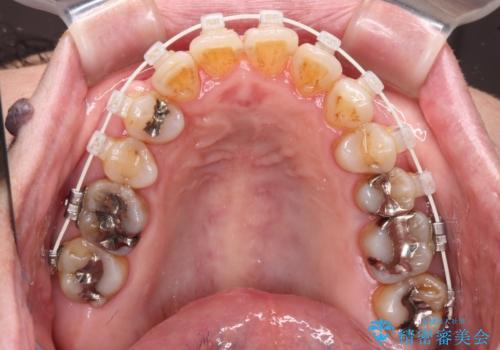

八重歯と形の悪い前歯 矯正治療とセラミック治療

- 長年前歯の歯並びで悩んでいるとのことで来院された患者様です。

機能的なことを考えると八重歯となっている犬歯は抜歯せず、歯列を改善することが望ましいとされますが、数十年もの間犬歯がない咬み合わせで問題なく過ごしてきたため、八重歯を抜歯することで、手っ取り早く歯列を改善することとしました。